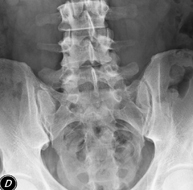

- Pelvis X-ray

This procedure uses X-ray imaging to examine the pelvis, especially the pelvic bones.

- Sacroiliac X-ray

This procedure uses X-rays to examine the sacroiliac joints and rule out inflammatory, traumatic or degenerative diseases.

- Lumbar spine X-ray

This technique uses X-ray rendered imaging to examine the lumbar spine. Indicated for: sciatica, trauma, lower back pain.